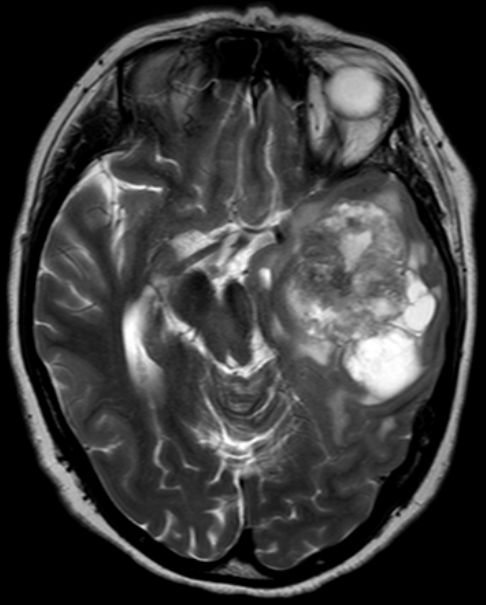

Glioblastom im Tempoallappen |

48-jährige Frau mit Übelkeit und Kopfschmerzen auf.

Kurze Bewusstlosigkeit.

Später Gedächtnisstörungen, Sprachstörungen und Verhaltensauffälligkeiten.![]() |

![]() |

![]() | ||||